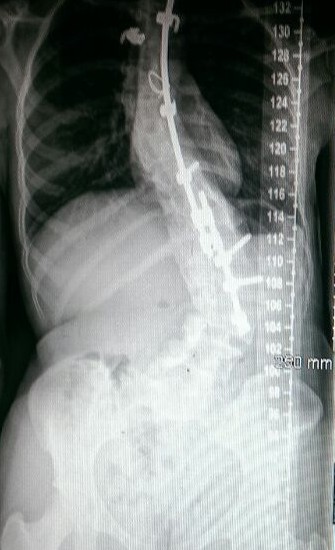

“The morning of surgery came. Saying goodbye to your loved ones and being wheeled into a room to be put asleep is a sinister feeling and one that I will never forget. I have grown such a strong bond with the nursing staff at Cappagh that they too shed a few tears for me; they know how much I’ve been through. Surgery started at 8am and I was awake and groggy by 5:30pm that evening. Morphine does strange things to the brain; you hallucinate and see things which can be a bit frightening. I was unbelievably stiff and swollen. A few days later a young doctor got talking to me, he was so excited about me having so much metal inside my body. He wheeled me over to a big monitor to show me my latest x-ray; the colour ran from my face. I couldn’t actually believe that this was MY body. It looked like something from a horror film.